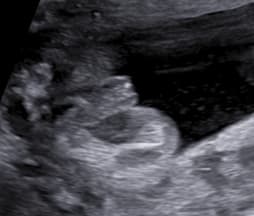

Chlapeček